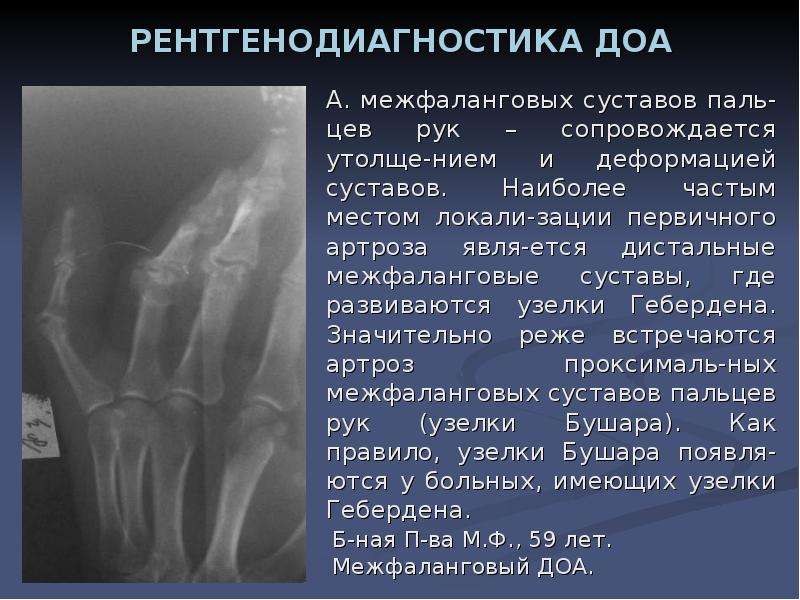

Симптомы и лечение остеоартроза узелков Гебердена: фотогалерея